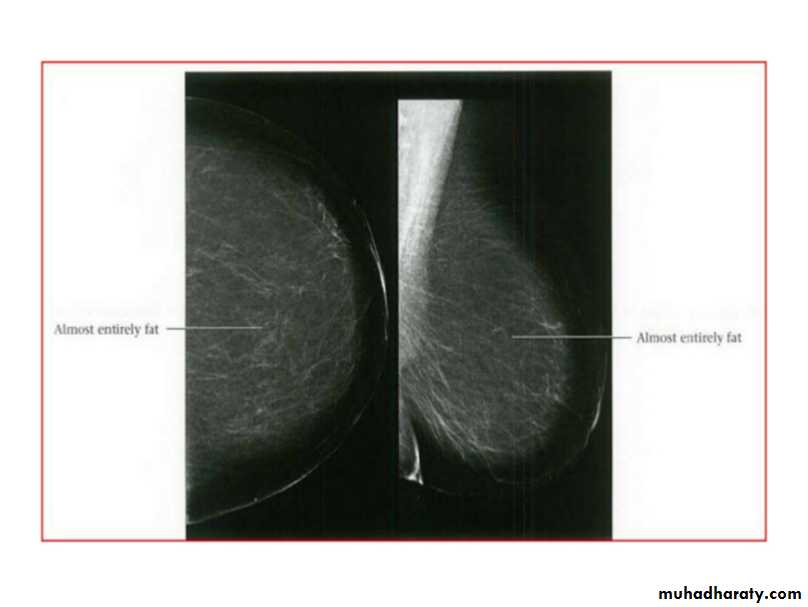

Breast density & who can U detect a mass lesion

Your mammogram report must take in consideration & assessment the breast density. Breast density is based on how fibrous and glandular tissue tissues are distributed in your breast, vs. how much of your breast is made up fatty tissue.

Dense breasts are not abnormal, but they are linked to a higher risk of breast cancer. We know that dense breast tissue can make it harder to find cancers on a mammogram. Still experts do not agree what other tests, if any, should be done in addition to mammograms in women with dense breasts who aren’t in a high-risk group (based on gene mutations, breast cancer in the family, or other factors